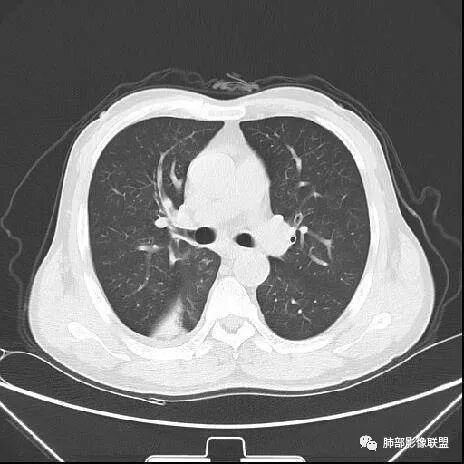

南边:紧贴着斜裂过来的一个病灶,它的特点是:外围大,内带小。它整个下叶背段体积与对侧相比稍微缩小一点,但是缩小地不是很厉害。外支朝前下走了,仔细看血管,肺动脉走行自然,直达远端。远端实变区是肉芽肿成分,稍微有一点低密度,没有明显坏死,稍微有一点点坏死。而且附近有很多卫星灶,附近很多斑片影,有一些明显有气道壁增厚,细支气管炎的特点,还有就是下叶其他段很多斑片状影。换个角度,第一如果是肺癌,刚才看到PET-CT提示肺癌伴阻塞性肺炎,这个是不符合的。第二如果是肺癌阻塞性肺炎,近端血管肺动脉走行不会那么自然集聚的,这个是不符合的。理由是:如果这个病灶是肺癌,那么明显属于中央型肺癌,中央型肺癌的特点是近端大,远端小,近端是一个肿块,远端阻塞,远端阻塞是阻塞性炎症或者不张,它应该体积缩小,斑片状实变,不会这么密实。刚才有老师提到支气管,这个片有缺陷的地方,给的图像好像那层,如果把其他图像拿开再重叠一下。

如果是单纯看这幅图像,会觉得背段外侧支气管分支堵塞的,但是看下面这层图

南边:你就发现外侧支气管朝下走的分支非常自然,通畅的。

南边:这个肺门区,11区和7区都有一些淋巴结,淋巴结的形态不是类圆形,而是梭形的。这个病灶给的图比较少,个人倾向,第一强化非常均匀,肉芽肿性病变;第二,里面血管走行非常自然,远端大近端小,倾向炎性,特别是下面还有斑片状影,非阻塞远端,支气管远端病灶下叶背段,其他段也有,所以我倾向炎性;另外,它里面整个走行符合支气管树爬行征,我倾向结核可能,首先我定在炎性,其次有没有结核的可能。

鉴别诊断:肺炎性肺癌,胸膜下起源,外围大,局部占位效应,有膨隆有收缩,这个不太支持。支气管走行里面没有看到支气管进入很自然堵塞的粘液栓的特点。附近这些磨玻璃影,它的磨玻璃影要么边界清楚,要么由内朝外蔓延的,而不是沿着支气管束蔓延的。而且附近斑片状影,有些似乎有结节感,但是大部分不是,它不是我们常见的磨玻璃样结节,有些有,导致像腺泡样结节那种椭圆的沿着血管束分布的,我会把肺炎型肺癌放在待排。

右肺下叶背断肿块,外围大,内带相对狭长         远端有膨隆,边缘模糊、凹凸不平         血管走形自然,病灶近端支气管通畅,沿支气管树蔓延         周边有多发病灶,多为磨玻璃密度且边界不清。

轻度强化         PET-CT:SUV 7.5,高摄取